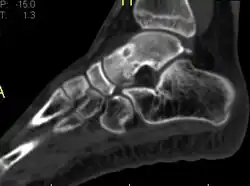

Radiographs in osteoid osteoma typically show a round lucency, containing a dense sclerotic central nidus (the characteristic lesion in this kind of tumor) surrounded by sclerotic bone. The nidus is seldom larger than 1.5 cm.

The lesion can in most cases be detected on CT scan, bone scans and angiograms. Plain radiographs are not always diagnostic. MRI adds little to the CT findings which are useful for localisation. Radionuclide scanning shows intense uptake which is useful for localisation at surgery using a hand held detector, and for confirmation that the entire lesion has been removed.[8][9]

1 a. Osteoid osteoma (front view) showing cortical thickening mid-tibia

1 b. Osteoid osteoma (side view): clearly seen by high resolution CT with a small well-defined lucent nidus in the mid tibial shaft.